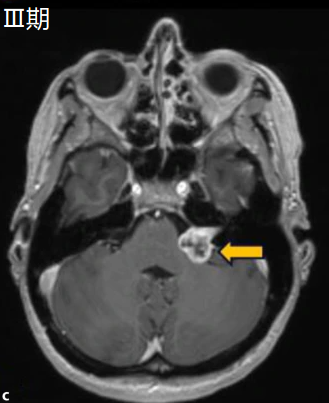

- Ⅲ期:脑干受压期

中型肿瘤,肿瘤直径为15-29mm,肿瘤开始接触脑干,但未产生明显的压迫症状,但是由于压迫到邻近神经,开始出现面瘫、面部疼痛麻木、共济失调、步态不稳等症状。